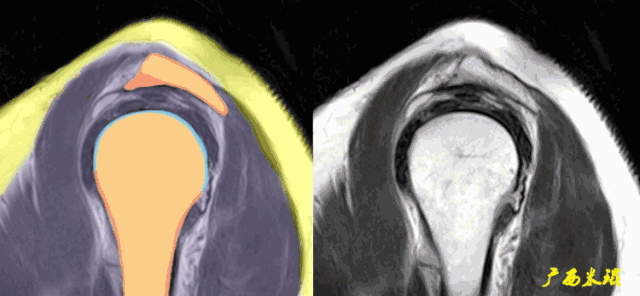

3、轴位:平行于关节盂/垂直于盂肱关节,主要评估盂唇,同时兼顾肩胛下肌、冈下肌及小圆肌。